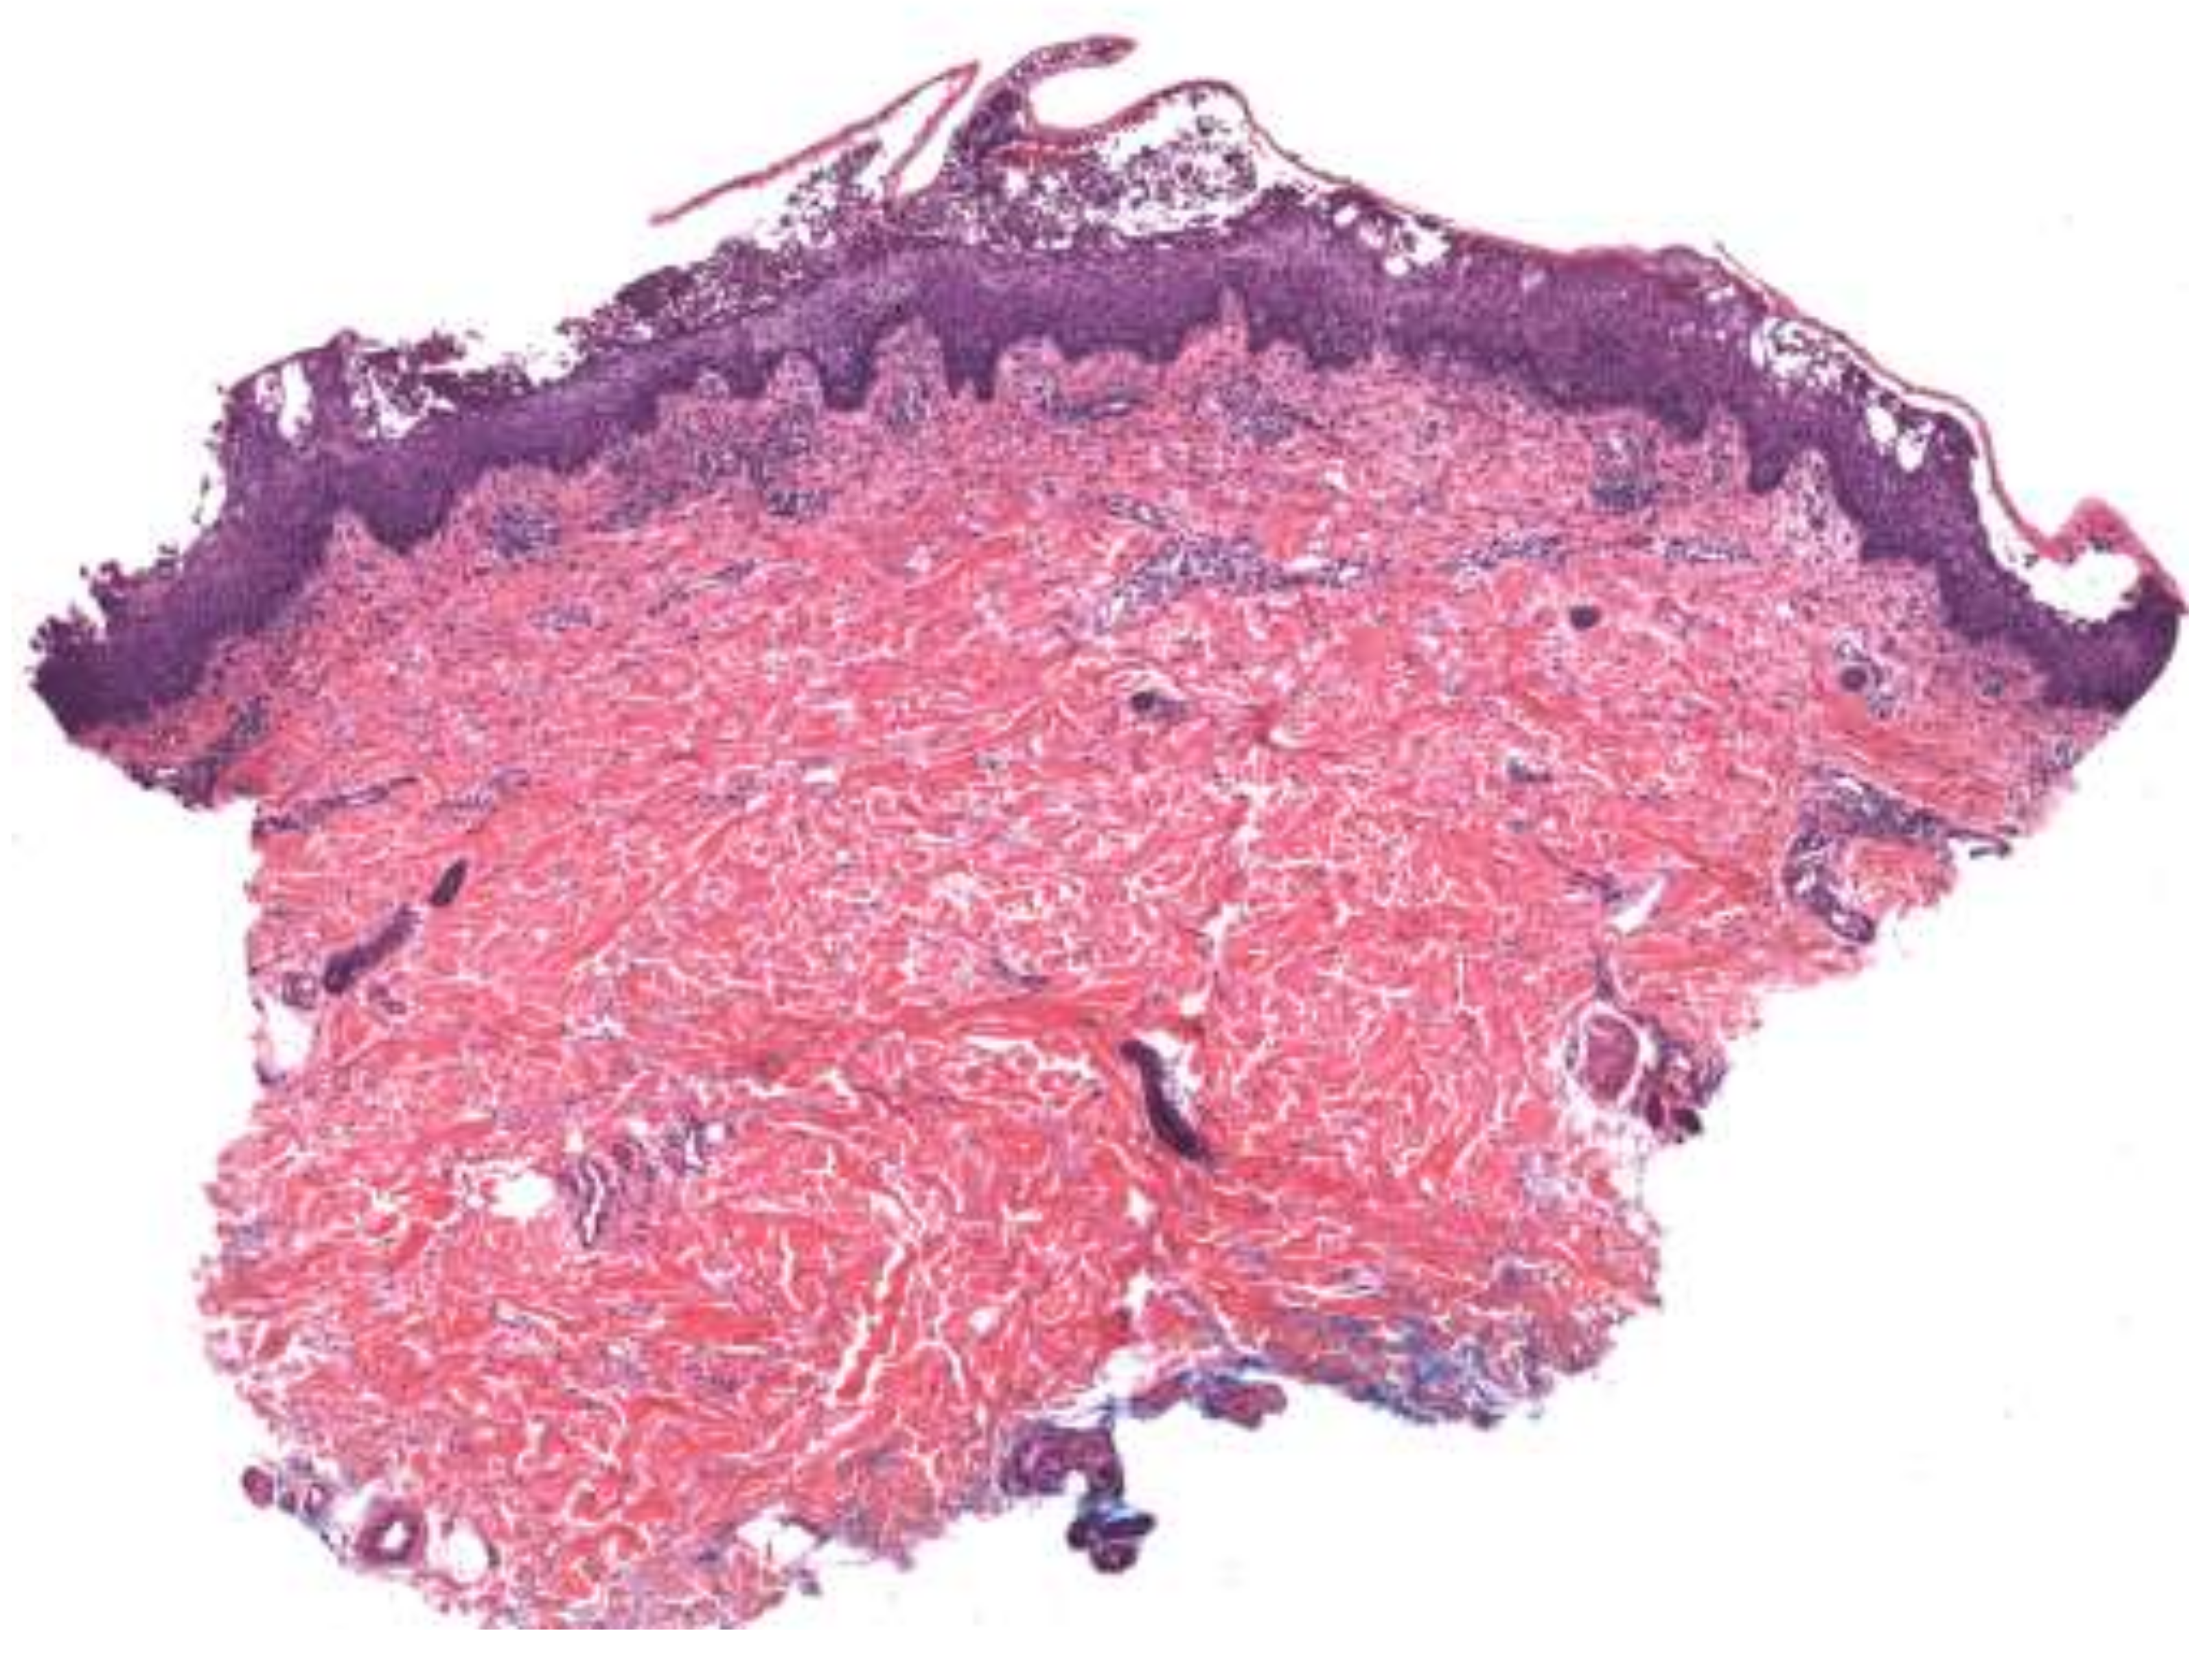

4. Histopathologic Features

| Generalized pustular psoriasis (GPP) | All PP subtypes contain sterile pustules [3]. Disseminated, painful erythematous lesions covered with aseptic pustules [3,8]. Severe systemic symptoms, including fever, malaise, fatigue, and arthritis, may be present [3,4]. | Fifth decade of life with slight female predominance [4]. | Pathogenesis: Disruption of the interleukin-36 pathway plays a major role (mutations in IL36RN), although there is significant heterogeneity in the gene pathways implicated [3,9,10]. The innate immune system, environmental factors, and genetic susceptibility all contribute [7]. Histopathology: Spongiform pustules of Kogoj in the epidermis and microabscesses of Munro [3,4]. Parakeratosis and psoriasiform hyperplasia [8]. | Topical corticosteroids, oral retinoids (i.e., acitretin), cyclosporine, methotrexate, TNF-α inhibitors (i.e., adalimumab), anti-IL-17 monoclonal antibody (i.e., secukinumab), anti-IL-23 monoclonal antibody (i.e., guselkumab), anti-IL-1β monoclonal antibodies (i.e., gevokizumab and canakinumab), IL-1R inhibitor (i.e., anakinra), PDE-4 inhibitor (i.e., apremilast) [3,4,7,9,11,12,13,14]. |

| Acute generalized exanthematous pustulosis | Sterile, pin-sized pustules overlying edematous and erythematous skin. Often appears on the face or intertriginous areas before spreading to the trunk and limbs [17]. Acutely accompanied by fever, neutrophilia, and eosinophilia [18]. | More common in adults with a slight female predominance [17]. | Pathogenesis: Drug-specific T-cell predominantly infiltrates with neutrophil accumulation mediated by IL-8 and GM-CSF [19,20,21]. Th17 cells are also involved in neutrophil activation [21]. Mutations in IL36RN found in some patients [20]. Histopathology: Spongiform subcorneal or intraepidermal pustules ± necrotic keratinocytes, vacuolar interface dermatitis, dermal eosinophilia, psoriasiform hyperplasia [17,22]. | Typically resolves within 2 weeks of discontinuation of the offending drug [20,23]. Topical steroids are often used for symptomatic relief [20]. Systemic corticosteroids or cyclosporine are useful in severe cases or with extracutaneous involvement [24,25]. |